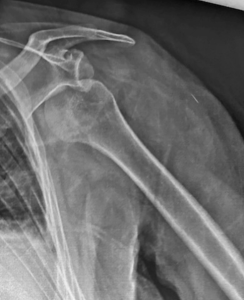

Epaule